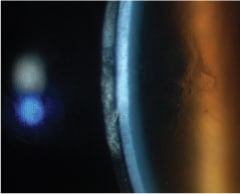

Figure 1 was taken after the patient had worn the LDS lenses for about four hours. Antibiotic ointment applied to the lids and cornea was not successful. We felt that the fit of the lenses could be improved.

Figure 1. Patient's cornea following wear of a large-diameter scleral lens for four hours.